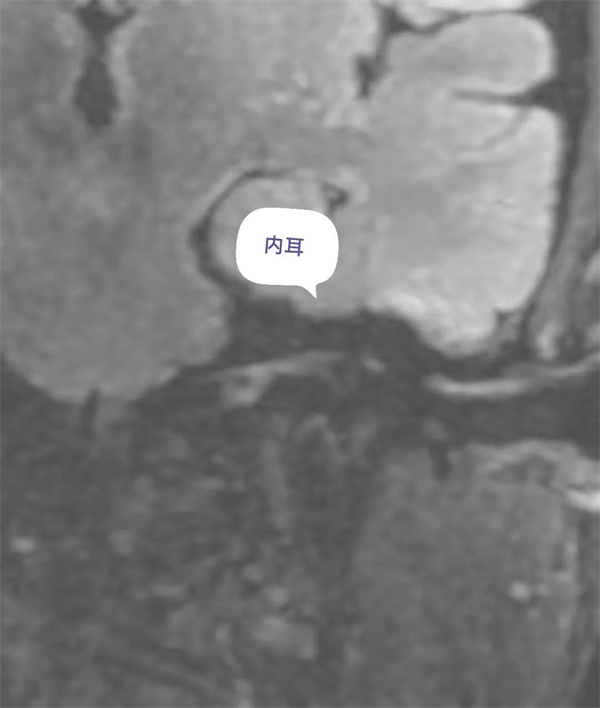

患者面肌痙攣,聽力減弱,行內(nèi)耳磁共振成像檢查。(如下圖所示)。

圖11:增強前磁共振內(nèi)耳圖。